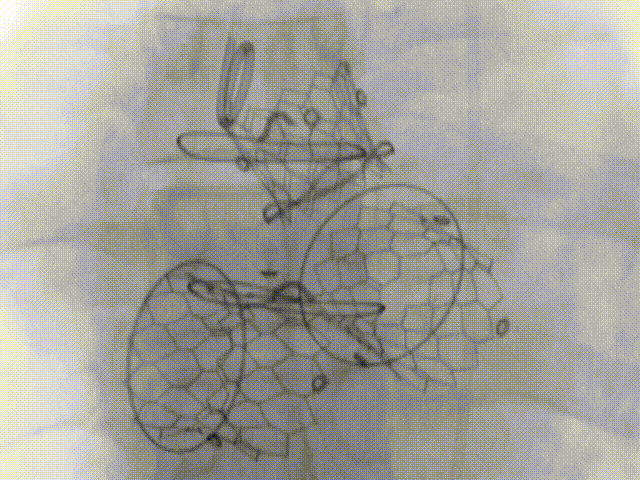

手术结束造影显示三个新瓣膜正常工作

3月5日,沪豫联合手术团队为患者实施了主动脉瓣、二尖瓣、三尖瓣联合“瓣中瓣”置换手术。由于患者病变复杂,团队采用了三种不同路径植入三个瓣位。首先经左侧股动静脉分别穿刺置入主动脉根部猪尾导管和临时起搏电极,再穿刺右侧股动脉,顺利完成23毫米主动脉瓣“瓣中瓣”植入。然后经心尖途径,顺利完成27毫米二尖瓣“瓣中瓣”植入。最后穿刺右侧股静脉,成功完成29毫米三尖瓣“瓣中瓣”植入。经主动脉、左室、右室分别造影以及TEE检查,3枚瓣中瓣植入位置完美,瓣膜开合正常,压差均在理想范围内,无瓣中及瓣周返流,双侧冠脉显影理想。术中血流动力学平稳,无传导阻滞和流出道梗阻等并发症发生,几乎无出血。手术取得了圆满成功!